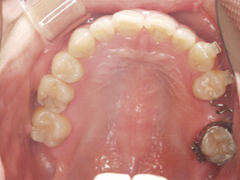

写真(3)

矯正治療後インプラント治療にて補綴

- 治療内容/矯正治療後隙間を一カ所に集め,インプラント1本ずつ3カ所にて補綴治療で噛み合わせを改善